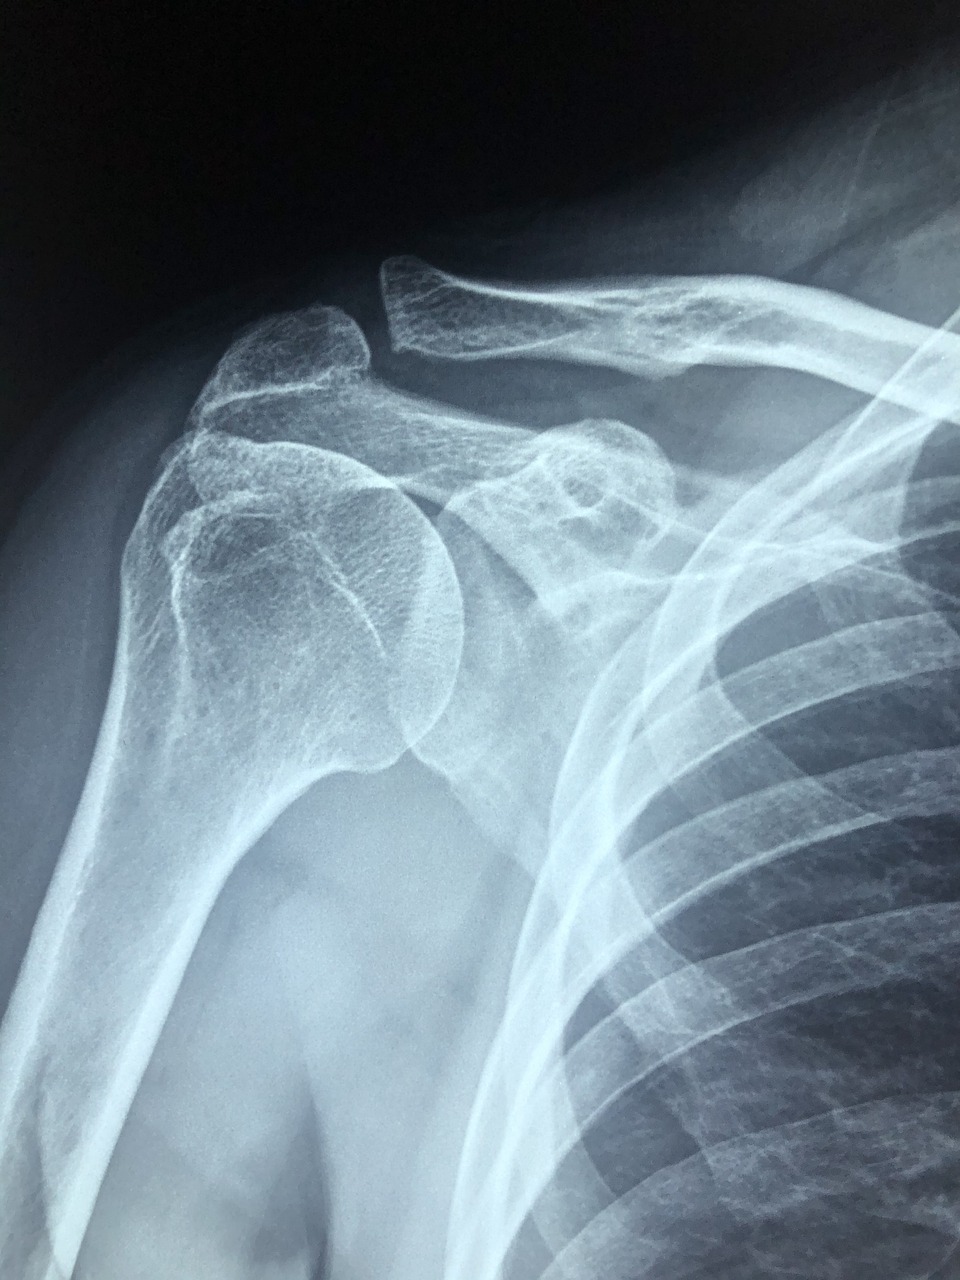

MRI는 자기공명영상(Magnetic Resonance Imaging)의 줄임말로, 회전근개 파열, 염증, 석회화, 힘줄 손상 여부를 확인하는 데 가장 정밀한 검사입니다.

X-ray나 초음파로는 보이지 않는 연부조직까지 확인할 수 있기 때문에, 정확한 진단과 수술 여부 결정에 중요한 역할을 합니다. 어깨 회전근개 MRI는 특히 50대 이후 어깨통증이 반복되거나, 팔을 올릴 때 극심한 통증이 있을 때 우선적으로 고려해야 할 검사입니다.